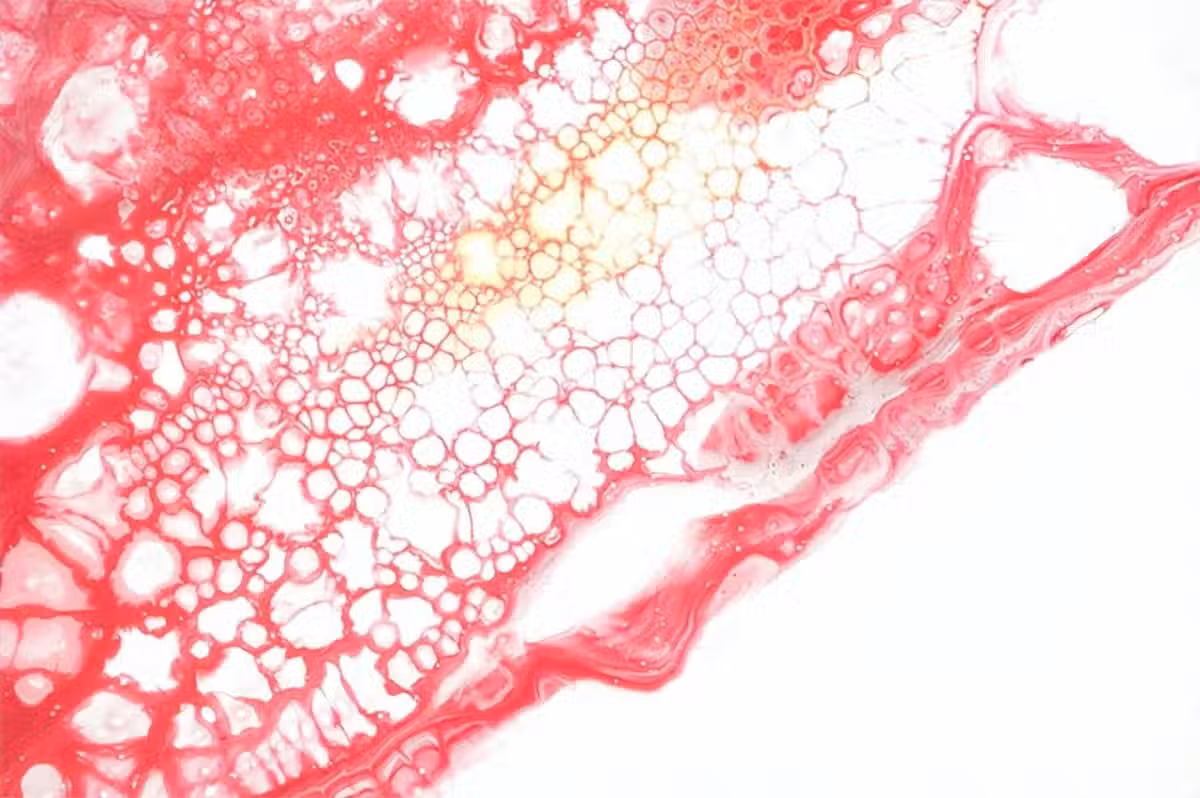

脂肪組織通過產生一種特有的激素,即「血管分泌」信號(脂肪因子),積極參與維持血管穩態。除了脂肪因子,脂肪組織還會分泌各種形式的DAN片段、脂質和蛋白質來幫助其實質性的內分泌活動。

脂肪細胞的三個主要功能,脂質存儲、內分泌功能和對胰島素的反應性,任何一個受到限制都會對人體整體的代謝平衡產生巨大影響。而我們上文已經介紹,大腦作為一種高度代謝的器官,特別容易受到外周代謝的影響,其中就包括由脂肪組織功能障礙引起的變化。

第一點就是脂肪組織引起的肥胖會顯著增加腦梗的發生機率。

目前有廣泛研究已經證實,肥胖是腦梗重要的危險因子之一,大腦內部脂肪的增多會加重主動脈的堵塞情況,從而增加腦梗發生機率。而且脂肪的過度攝入會導致心外膜脂肪組織的厚度增加,而有研究表明,心外膜脂肪組織的厚度增加會增加腦梗發作的風險。